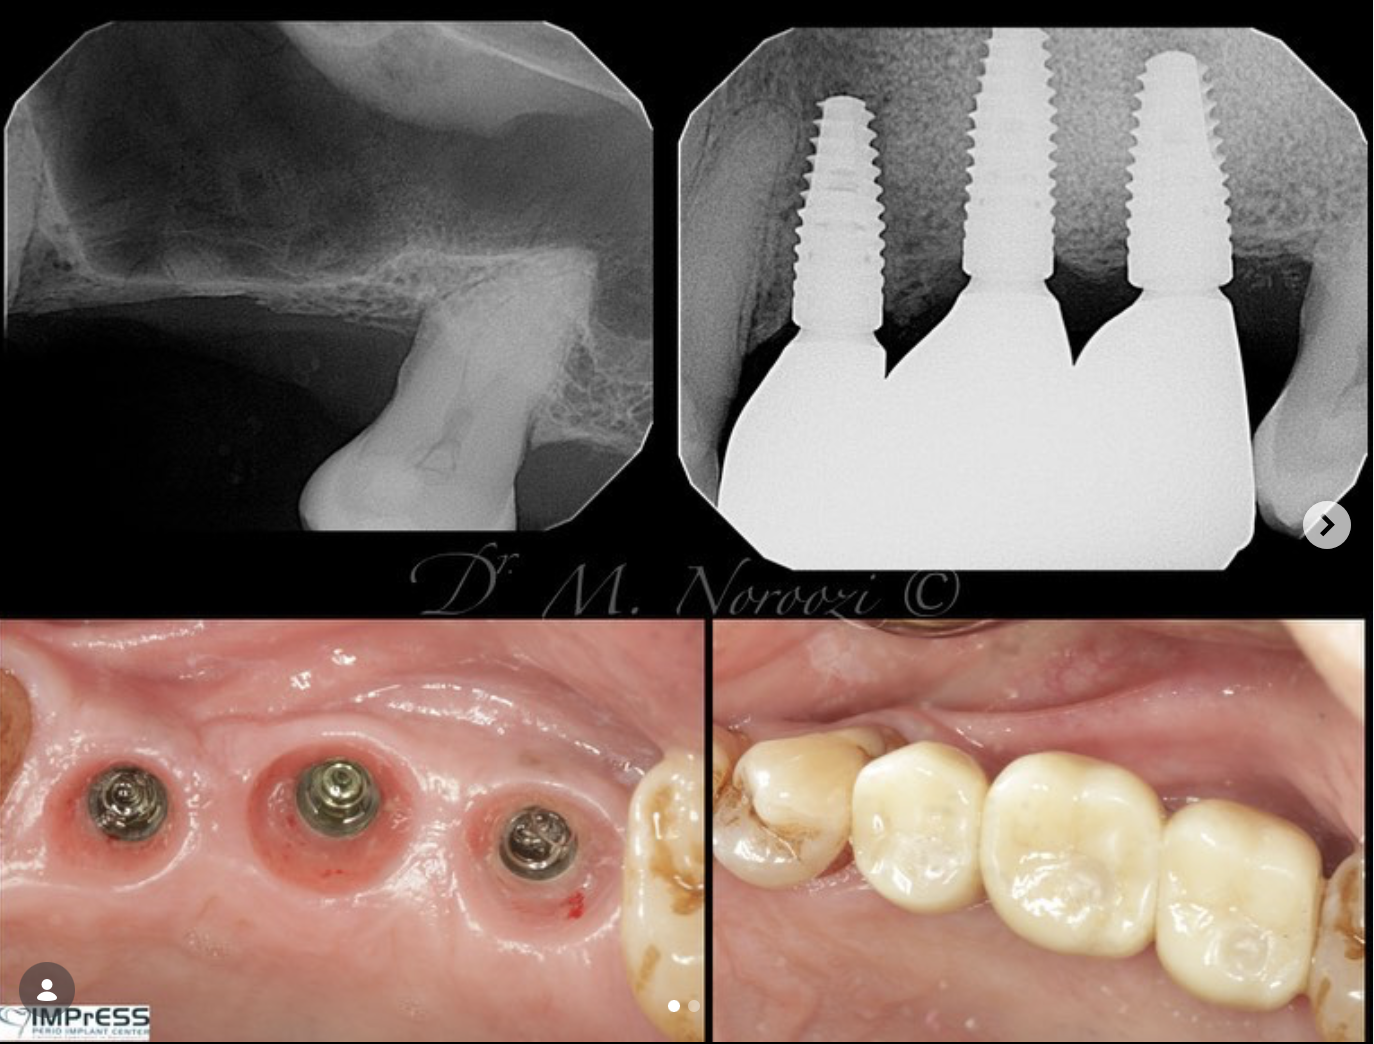

CBCT Guided Implant Surgery – Restoratively Driven Implants

Multiple Dental Implants IMPrESS Perio Implant Center Burnaby Implant Specialist Vancouver Implant Center Dr. Mehdi Noroozi Implant Specialist in BC